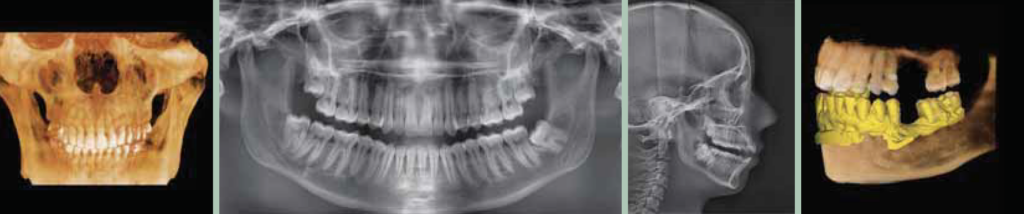

Computerul Tomograf cu Fascicul Conic (CBCT)3D

Este o tehnologie de ultima generatie in domeniul imagisticii ce permite vizualizarea in plan tridimensional a zonelor scanate. Folosind un fascicul conic de raze X, scanerul CBCT are nevoie de o unica rotatie in jurul pacientului pentru a prelua sute de imagini ale zonei de interes, acestea fiind apoi reconstruite cu ajutorul unui software de imagistica, in vederea obtinerii modelului virtual 3D al pacientului.

Computerul Tomograf cu Fascicul Conic prezinta numeroase avantaje in comparatie cu un simplu film panoramic sau cu tomografiile obtinute cu ajutorul CT-urilor clasice.

In primul rand tomografiile computerizate obtinute cu ajutorul CBCT furnizeaza medicilor mult mai multe informatii decat cele obtinute in mod normal. Densitatea osoasa, dimensiunile la scara 1 : 1 a dentitiei si a structurilor invecinate sunt doar cateva din informatiile suplimentare obtinute prin efectuarea unei tomografii cu ajutorul CBCT, informatii vitale in stabilirea unui diagnostic si a unui plan de tratament optim.

Intreaga procedura este de foarte scurta durata, iar gradul de expunere la radiatii in cazul unei tomografii computerizate realizate cu CBCT este echivalentul unei radiografii panoramic. Pentru vizualizarea modelului 3D, medicii si specialistii beneficiaza de un curs si software gratuit cu ajutorul caruia imaginile pot fi manipulate pentru a arata diverse unghiuri, pot masura adancimi, grosimi, densitati, pot selecta numai anumite tesuturi etc.